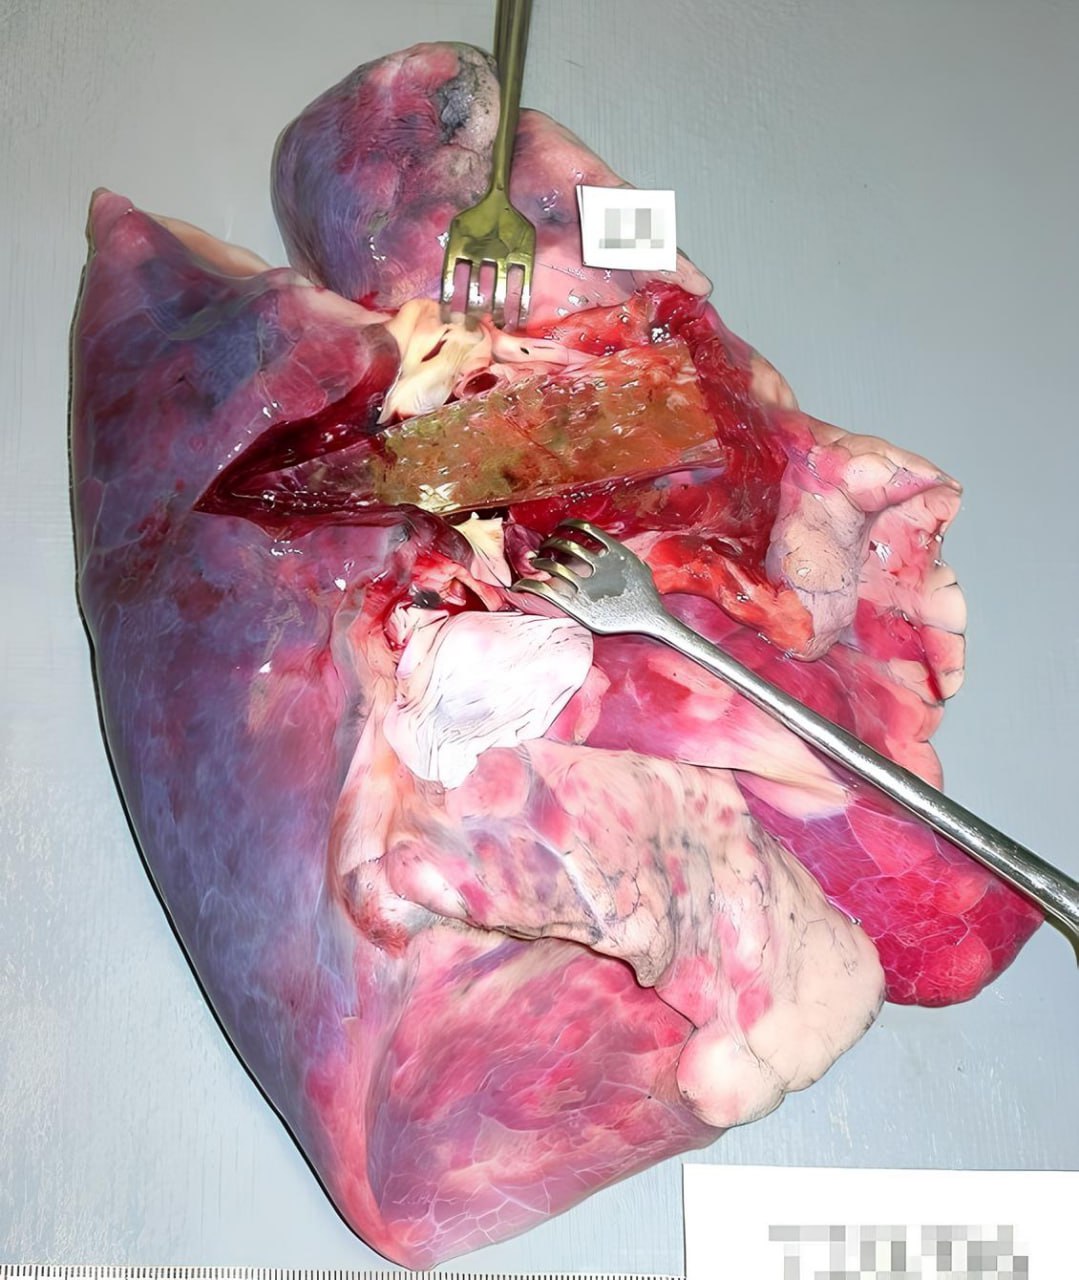

У пациента наблюдается обширная гангрена лёгкого, орган словно прожевали и выплюнули

А ещё — рахеопищеводный свищ: патологическое отверстие между пищеводом и трахеей, через которое пища и жидкость попадали прямо в дыхательные пути. Процесс усугублялся множественными метастазами во все группы лимфоузлов и в печень.

Смертельный «коктейль», где каждый компонент несовместим с жизнью.